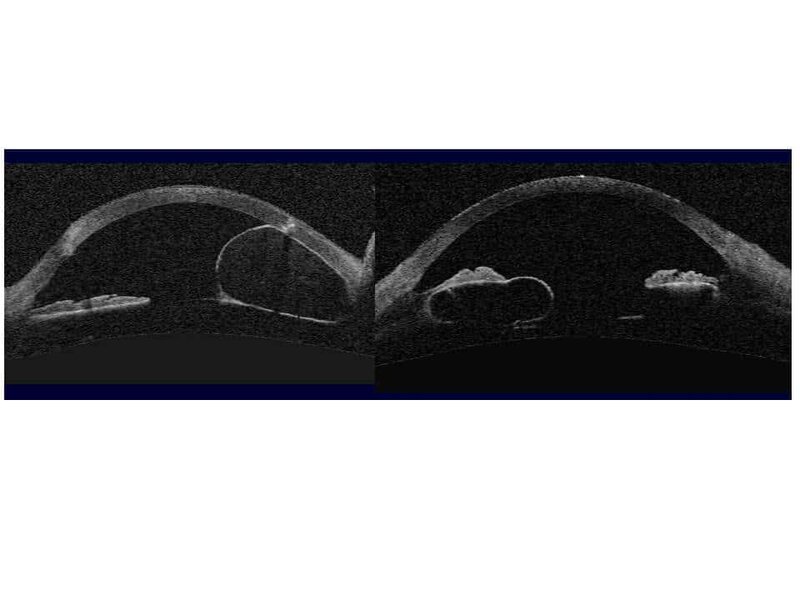

Volumineux kyste iriens, à la fois développés aux dépends du stroma irien (cliché de gauche) et de l’épithélium pigmenté irien (cliché de droite), et entrainant une fermeture localisée de l’angle irido-cornéen avec apposition de l’iris contre la trabéculum et l’endothélium cornéen.

(Cliché dû à l’amabilité de Aptel F, Grenoble).